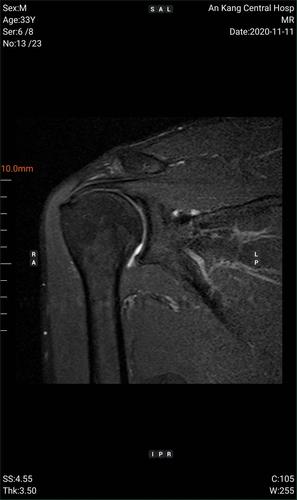

冈上肌肌腱撕裂核磁图,冈上肌肌腱损伤伴积液

冈上肌mri目前是诊断肩袖疾病中最常用的检查,可以直观的观察肩袖肌腱

冈上肌肌腱损伤伴积液